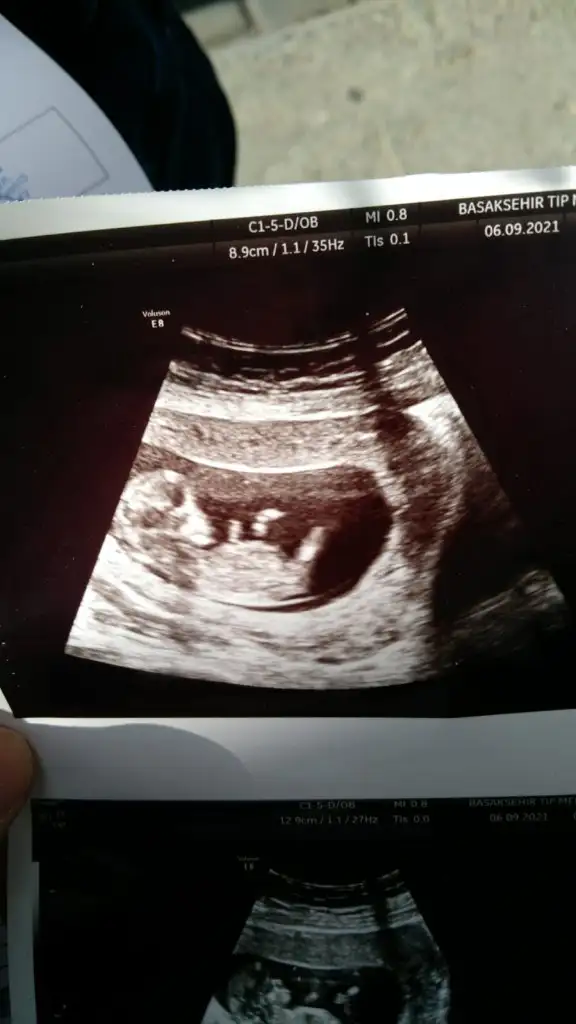

• IMG-20210906-WA0004.webp

IMG-20210906-WA0004.webp

17,8 KB · Görüntüleme: 89

• IMG-20210906-WA0005.webp

IMG-20210906-WA0005.webp

23,6 KB · Görüntüleme: 107

Ikra meyra Ikra meyra canım ilk çocuğumun cinsiyetini bilmiştin buna da bakabilir misin? Şimdiden çook teşekkür ederim🥰